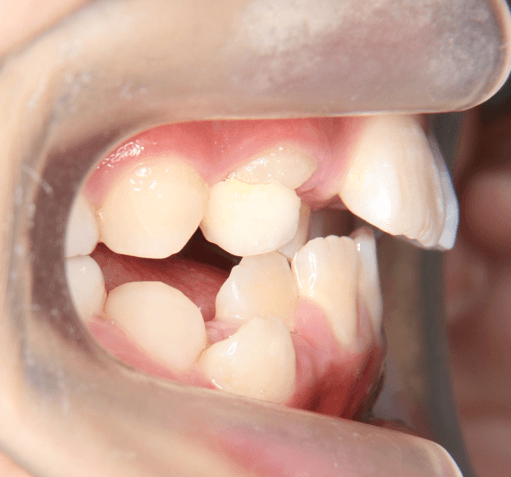

| 年齢・性別 | 8歳11ヶ月の男児 |

|---|---|

| 主訴 | 上顎の永久歯の位置がおかしいとのことで来院。萌出していない右上の前歯の状態に不安を抱えられていました。 |

| 治療期間・回数 | 約3年2ヶ月 |

| 費用 | 440,000円(税別) |